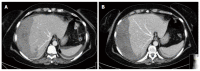

Sub capsular hepatic haematoma is a rare complication after endoscopic retrograde cholangiopancreatography (ERCP). Exact pathological mechanism is still unclear and few reports are nowadays available in literature. We report the case of a 58-year-old woman with recurrent episodes of upper abdominal pain, nausea and vomiting. On the basis of laboratory exams, abdomen ultrasound and magnetic resonance imaging she was diagnosed with a common bile duct stone. Endoscopic biliary sphincterotomy was performed. On the following day the patient complaint severe abdominal pain with rebound and hemodynamic instability. A computed tomography scan reveal a 14 cm × 6 cm × 19 cm sub-capsular hepatic haematoma on the right lobe that was successfully managed via percutaneous embolization. Sub capsular liver haematoma is a rare life threatening complication after ERCP that should be managed according to patients' haemodynamic and clinic.